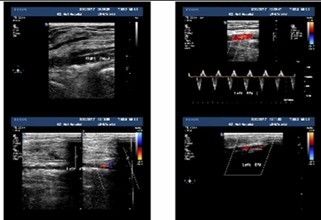

一般情况介绍 患者张XX,男,69岁,因“跌倒致左髋疼痛、活动障碍6天”入院。既往史:“糖尿病”15年,一直服“拜糖平”、“二甲双胍”治疗,血糖控制在 7~15mmol/L之间。高血压病史4年,最高达180/90mmHg,未系统服药治疗。曾有脑梗塞病史,2月前因“双侧颈动脉粥样硬化、右颈内动脉中 度狭窄”行右颈动脉支架成形术,现服用波立维、拜阿斯匹林联合抗血小板治疗。查体:左髋部无肿胀、瘀斑,关节活动受限,叩痛、压痛(+),左下肢外旋 60°畸形。双足多处皮肤破溃坏死,创面干燥,右足足背动脉搏动不明显。影像学资料:骨盆正位、左侧髋关节侧位示“1、左侧股骨颈骨折;2、骨盆骨质疏 松”(图1、2)。颈动脉超声示“双侧颈动脉粥样硬化伴多发斑块”(图3)。下肢动脉彩超示“双下肢动脉粥样硬化闭塞症声像;右侧胫前及左侧胫前、足背、 胫后动脉广泛狭窄(中-重度);右足背动脉狭窄(轻度)” (图4)。下肢静脉彩超示“左下肢深静脉血栓栓塞声像:左侧腓静脉(后一条)及左小腿多发肌间静脉完全栓塞。双侧股静脉及腘静脉血流缓慢。余双下肢深静脉 及大隐静脉近段未见明显异常声像” (图5)。心脏彩超示“主动脉硬化、主动脉瓣退行性变;左房增大,心内血流未见明显异常;左室收缩功能未见异常,舒张功能减退”。血生化指标:凝血四项示 “纤维蛋白原6.64g/L”,D-二聚体“1499ng/ml”。结合患者病史、体征及辅助检查,诊断“1、左股骨颈骨折;2、Ⅱ型糖尿病;3、高血压 病;4、脑梗塞后遗症;5、右颈动脉支架成形术后”。请内分泌科、心血管内科会诊,停用波立维、拜阿斯匹林,行降糖、降压、营养支持等对症治疗。入院后两 周在气管插管全麻下行“左侧人工股骨头置换术”,术程顺利。患者麻醉清醒后即嘱其行双下肢肌肉主动舒缩及膝踝关节屈伸活动,术后12h开始首次应用磺达肝 癸钠2.5mg皮下注射,以后每天以同等剂量皮下注射一次。患者术后5天即可在助行器帮助下下床活动,磺达肝癸钠持续用至10天停止,并防治感染、降糖、 降压、营养支持治疗。治疗期间每日观察患肢是否有肿胀情况,测量双侧大腿及小腿周径并记录。术后两周复查双下肢动静脉彩超,与术前结果相同;行肺部X线片 及CT检查,未见肺动脉栓塞征象。骨盆X线片示人工股骨头置换术后改变,人工假体位置佳(图6)。患者顺利出院,并恢复波立维、拜阿斯匹林联合抗血小板治 疗。

图4 下肢动脉超声示双下肢动脉粥样硬化闭塞征